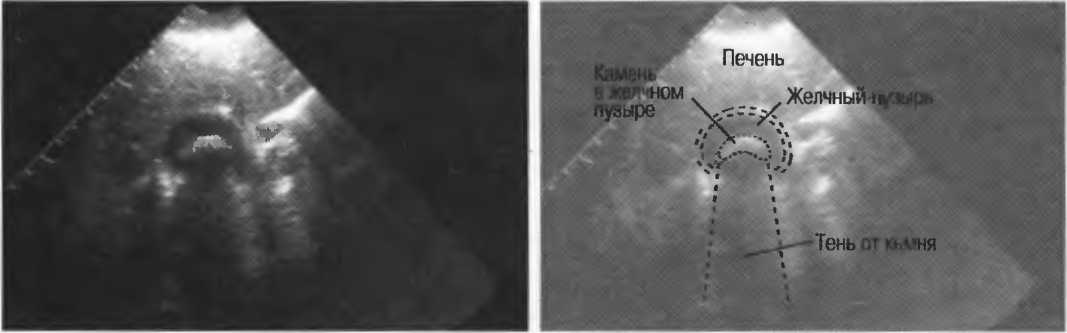

Рис. 17а. Большая акустическая тень за камнем в желчном пузыре.